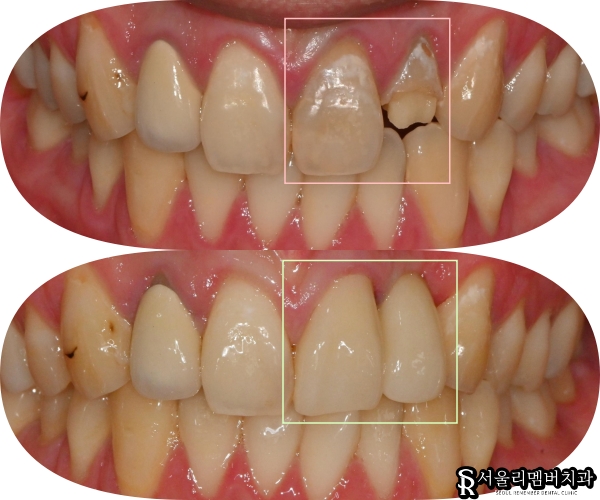

오늘 신대방 치과 에서 살펴볼 케이스는

상악 좌측 전치부 부위에서

복합적인 문제가 발생한 경우입니다.

먼저 중절치(21번)를 보면

정면에서 관찰했을 때

치면이 전반적으로 약해져 있는 상태였고,

안쪽 구개측에서 확인했을 때

상당한 크기의 충치가 진행되고 있었습니다.

그 옆의 측절치인 22번은

상황이 더 심각했습니다.

이가 부러진 상태였는데

파절된 양이 상당히 넓어서

남은 치질의 양이 얼마 없었습니다.

신대방 치과 에서

전치부 진료가 마무리된 모습을

보여드리겠습니다.

두 개의 앞니가 모두 자연스럽게 회복되어

인접한 주변 이들과 조화롭게 어울립니다.